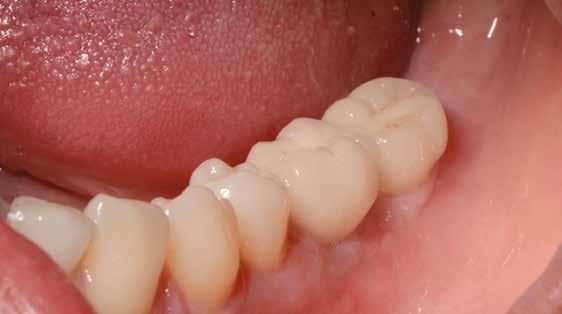

1. a–d. ábra: Műtét előtti állapot mind a négy páciensnél. 1. eset (a). 2. eset (b). 3. eset (c). 4. eset (d).

digitális implantátumtervezés követett (SICAT és Sidexis, mindkettő Dentsply Sirona; 1. ábra).

lási csavarokat (PEEK titáncsavarral) maximum 15 Ncm-rel húztuk meg (3–6. ábra). Az összes implantátum kiváló stabilitást mutatott (a mérésekhez Periotestet használtunk, a Medizintechnik Gulden jóvoltából), és teljesen osszeointegrálódott. Ezt a radiológiai vizsgálatok is megerősítették.